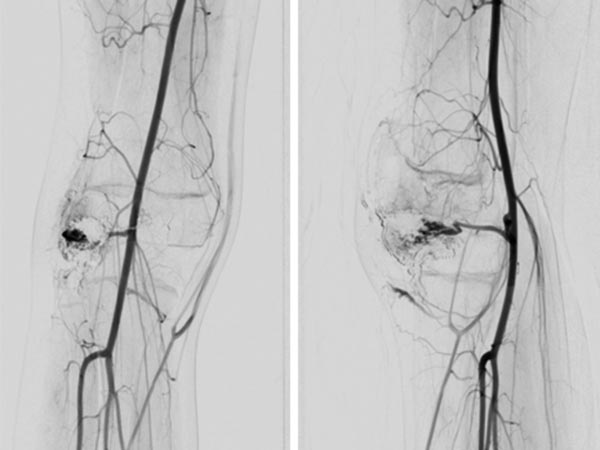

Digital subtraction angiography (DSA) of the knee (left AP projection, left lateral projection) shows an AVM with a rather spherical, aneurysmal nidus as well as another nidus intraosseously in the lateral tibial plateau. This very spherical, aneurysmal nidus together with the painful, progressive mass is suggestive of a PTEN hamartoma.

After successful embolization of the two AVM nidus parts, the radiographic overview images (left AP, right lateral projection) shows a complete cast specimen of the two portions caused by the embolic agent, the so-called cast. This consists of ethylene-vinyl alcohol copolymer, which contains radiopaque tantalum.

In the control DSA (left AP, right lateral) after embolization with ethylene-vinyl alcohol copolymer, no more perfusion is seen in the angiography even in a long series. The AVM is considered to be occluded.

The repeat DSA 4 months after the previous embolization (left AP, right lateral) shows an early, circumscribed recurrence. Especially in the case of AVMs associated with a PTEN hamartoma syndrome, patients must attend for follow-up at short intervals, as these AVMs in particular have a high tendency to recur.